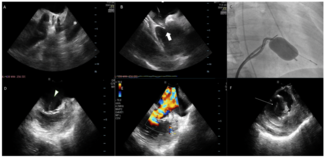

Alan Chan Ka Chun, MBBS; Kam-Tim Chan, MBBS, MD; Michael Lee, MBBS; Cheuk Bong Ho, MBBS; Ivan Wong, MBBS

Traditionally, percutaneous mitral commissurotomy (PMC) is performed under fluoroscopy only. In difficult cases, general anesthesia with transesophageal echocardiography (TEE) guidance is needed. Intracardiac echocardiography (ICE) enables...

An 89-year-old woman was referred for closure of a patent ductus arteriosus (PDA). Contrast-computed tomography showed Krichenko type C PDA with severe calcification.